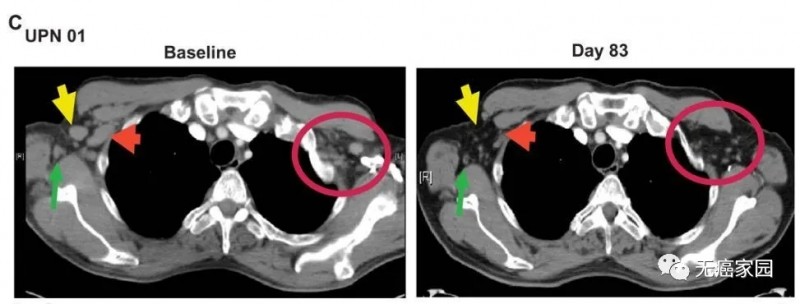

据悉,与Bill一同接受治疗的还有两位白血病患者,三人中,仅在单次治疗后就有两名患者体内的癌细胞被完全清除,呈现完全缓解,另一例为部分缓解。以下是一位患者接受治疗83天后的对比图,可见疗效格外令人惊艳!